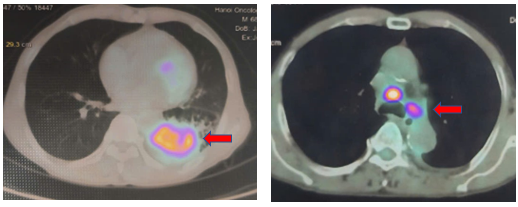

PET/CT: Khối mờ vùng rốn phổi trái kích thước 62x52x89 mm, thâm nhiễm bạch mạch, màng phổi, rãnh liên thùy, tăng chuyển hóa FDG SUVmax: 10,04. Nhiều hạch trung thất ở 2R, 4R, 5,6,7 hạch lớn nhất có đường kính 10mm tăng chuyển hóa FDG SUVmax: 11,49

Hình 3: Hình ảnh PET/CT: hình ảnh khối u phổi tăng chuyển hóa FDG SUVmax: 10,4 và hạch trung thất tăng chuyển hóa FDG SUVmax: 11,49, điển hình của tổn thương ác tính.